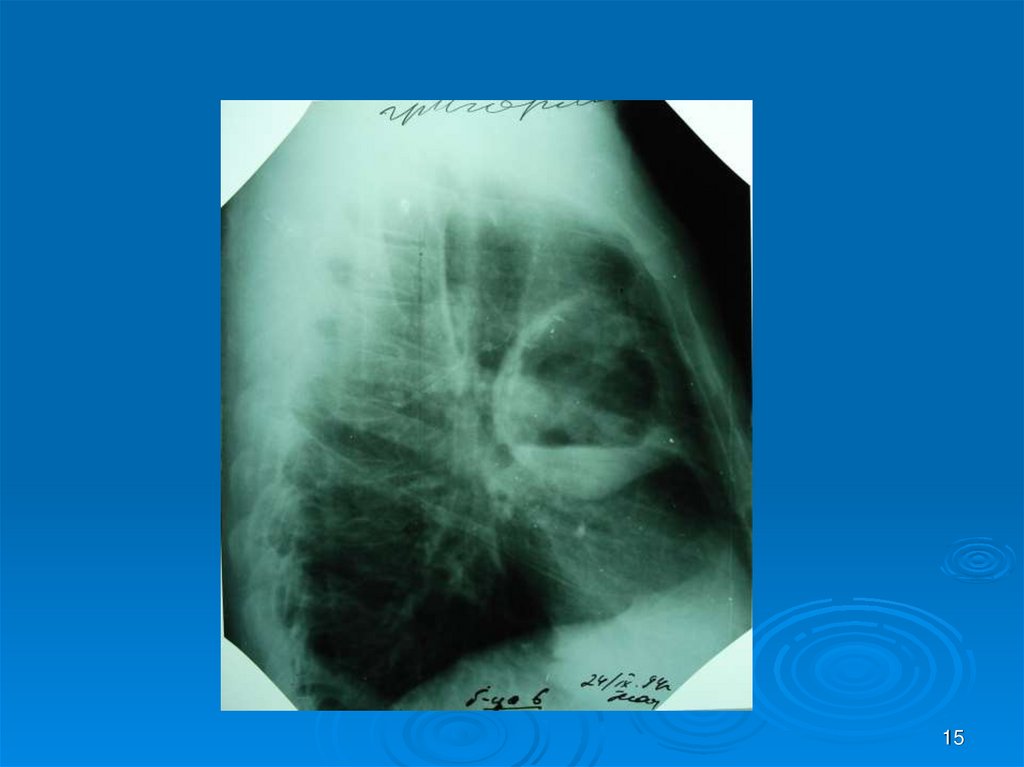

15.

15